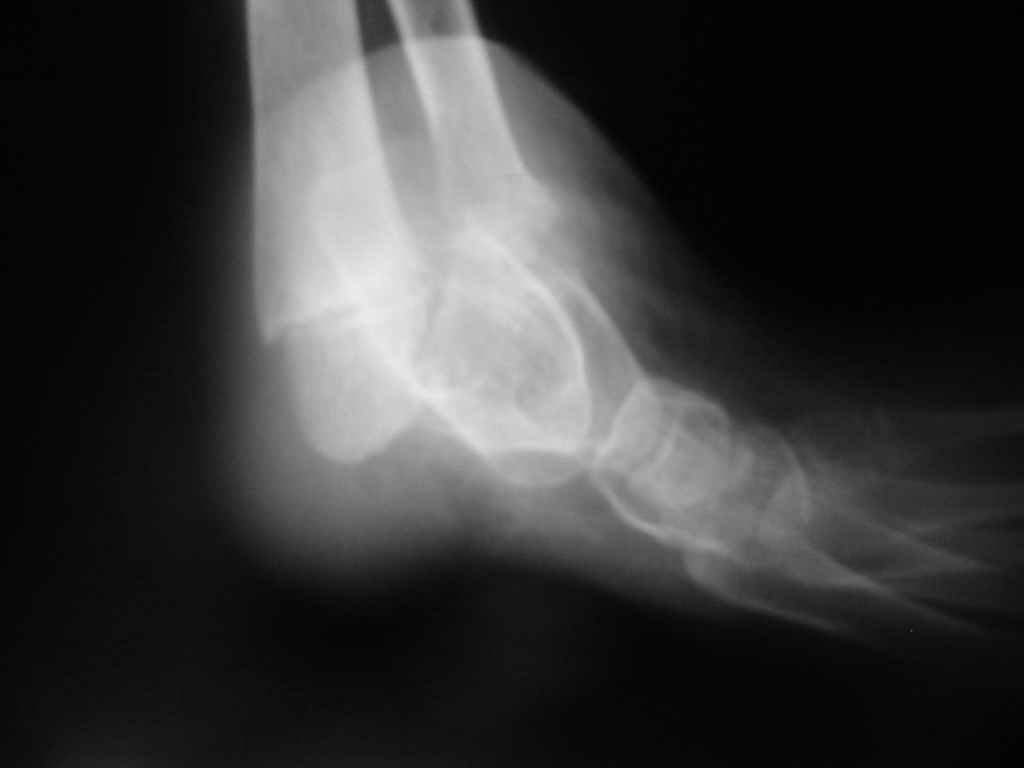

Судя по представленным фото и Рг граммам, у 13 летнего ребенка врождённая гемимелия большеберцовой кости, таранно-пяточный синостоз Из-за отставания в росте большеберцовой кости (остутствует дистальный эпифиз с зоной роста) произошла компенсаторная гиперофия малоберцовой кости, на которую приходится основная нагрузка (спонтанная тибиализация малоберцовой кости). Как результат дисбаланса осевого роста вторично возникла эквино-варусная деформация стопы. Продолжающийся рост ребёнка (до естественного закрытия зон роста) будет приводить к усугублению деформации по приведенным выше причинам.

Своё наблюдение только одно (ребёнка наблюдали и продолжаем наблюдать с рождения) и дважды оперировали: 1 этап выполнили проксимальный тиб/фиб фьюжн вторым этапом медиализация малоберцовой кости с таранно- малоберцовым синостозом и ещё предстоят этапы по удлинению тибиализированной малоберцовой кости.

В вашем случае я бы избрал следующую тактику:

Поднадкостничную остеотомию большеберцовой кости в средней трети с формированием синостоза с малоберцовой ( активно растущей) костью и второй уровень в области дистального тиб/фиб синдесмоза- достигается баланс роста( средне-медиальный и латеральный отделы) в области измененного голеностопного сустава. Коррекция эквино-варусной деформации стопы в аппарате после чрезкожной сегментарной тенотомии ахилова сухожилия. Дело

кропотливое и длительное.

Как резервный вариант может быть рассмотрена ампутация в верхней трети голени с изготовлением функционального протеза, если родители ребенка не настроены на длительную коррекцию и многоэтапную хирургию, родственники должны понимать, что абсолютного функционального результата даже после этапных операций достичь будет невозможно (аномальный голеностопный сустав, таранно-пяточный синостоз).